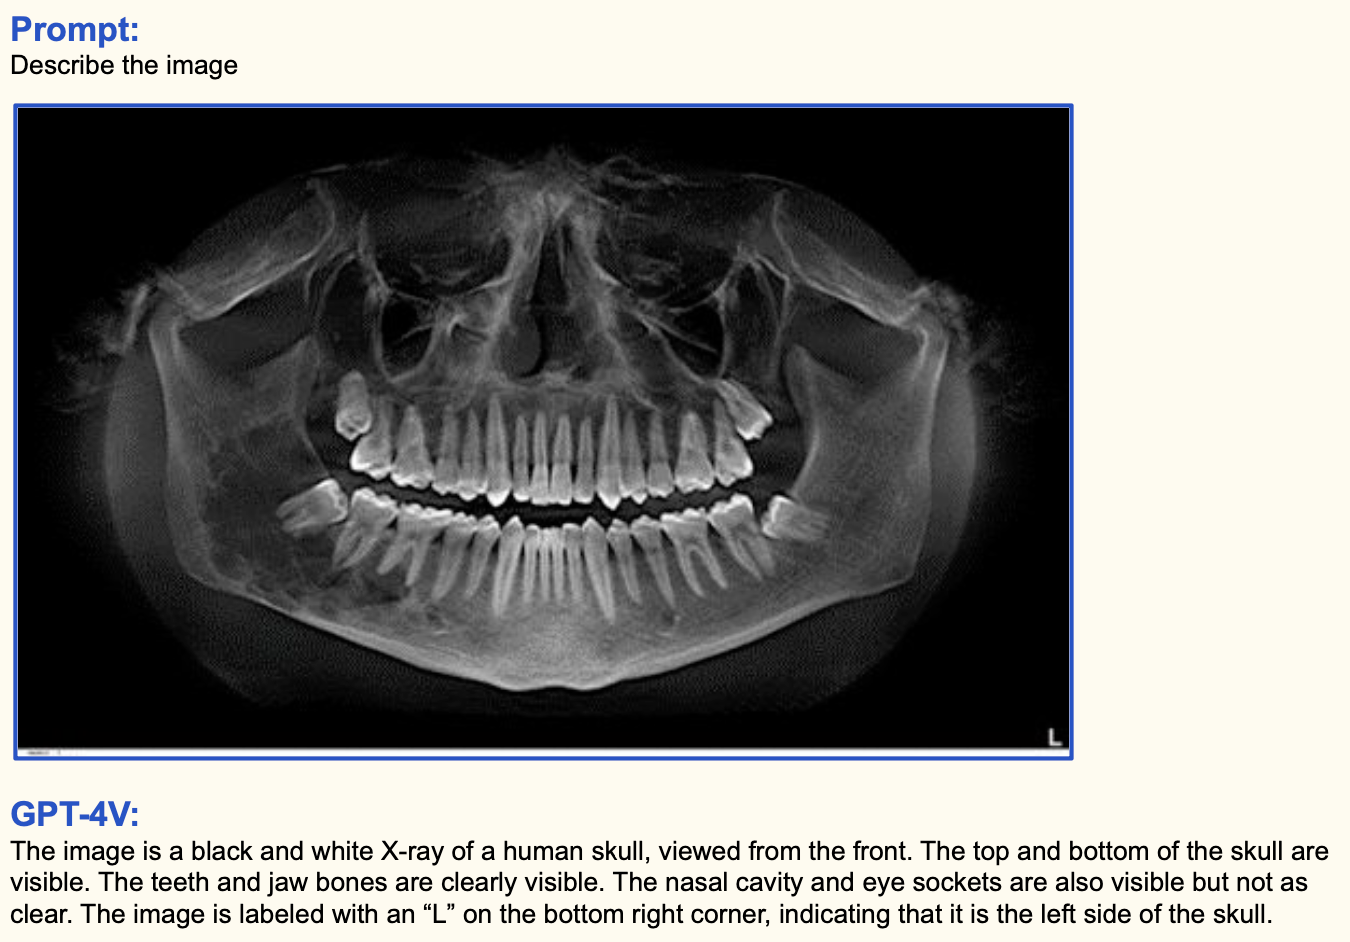

8. 의료 이미지 인식

GPT-4V는 의료 이미지도 인식을 잘합니다. 단순히 인식하는 것을 넘어서 의료 지식을 바탕으로 질문에 답해줍니다. 예를 들어서 치아 x-ray 이미지를 보고 "어느 사랑니가 가장 뽑기 힘들 것 같아?", "사랑니를 뽑을 필요가 있을까?" 등과 같이 의학 지식 없이는 답할 수 없는 질문들을 정확하게 답해줍니다. 어마어마 하네요.

신기하니까 몇 장 더보고 가겠습니다. 골절된 뼈 사진이랑 감염된 폐 CT 사진을 보여주고 무엇이 잘못됐는 설명해보라고 하면 잘 대답해줍니다. 대체 학습 데이터를 어떻게, 얼마나 많이 학습시켰길래 이렇게 잘나오는지 참... 대단합니다.

내용은 "GPT-4V 폼 미쳤다!" 한줄로 요약할 수 있을 것 같습니다. 전례없는 미친 성능을 보여주며 텍스트와 이미지의 경계를 깨버리네요. 특히 의료 이미지를 이해하고 전문적인 질문에 대답해주는 부분은 탄성을 자아냅니다.